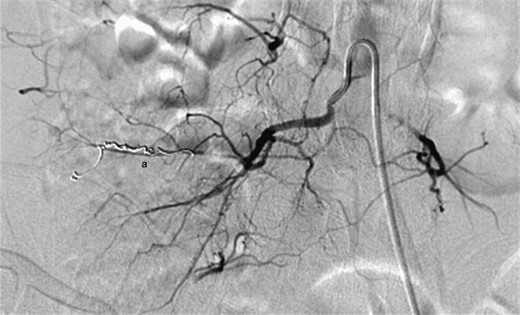

Examination on admission revealed an actively bleeding 2-cm wide stab wound in the right lumbar paraspinal region. A contrast-enhanced CT of the pelvis showed an enhancing lesion consistent with a pseudoaneurysm extending from a branch of a right lumbar artery (Figs 1 and 2). The patient was transferred to the interventional radiology suite where angiography confirmed the diagnosis (Fig. 3). The pseudoaneurysm was then successfully embolized using platinum microcoils (Fig. 4), which were positioned in the lumbar artery, proximal and distal to the origin of the pseudoaneurysm. The patient tolerated the procedure well and was discharged the following day without any further complication.

Digital subtraction angiography demonstrating successful embolization of the proximal and distal entry points of the pseudoaneurysm using platinum microcoils (a).